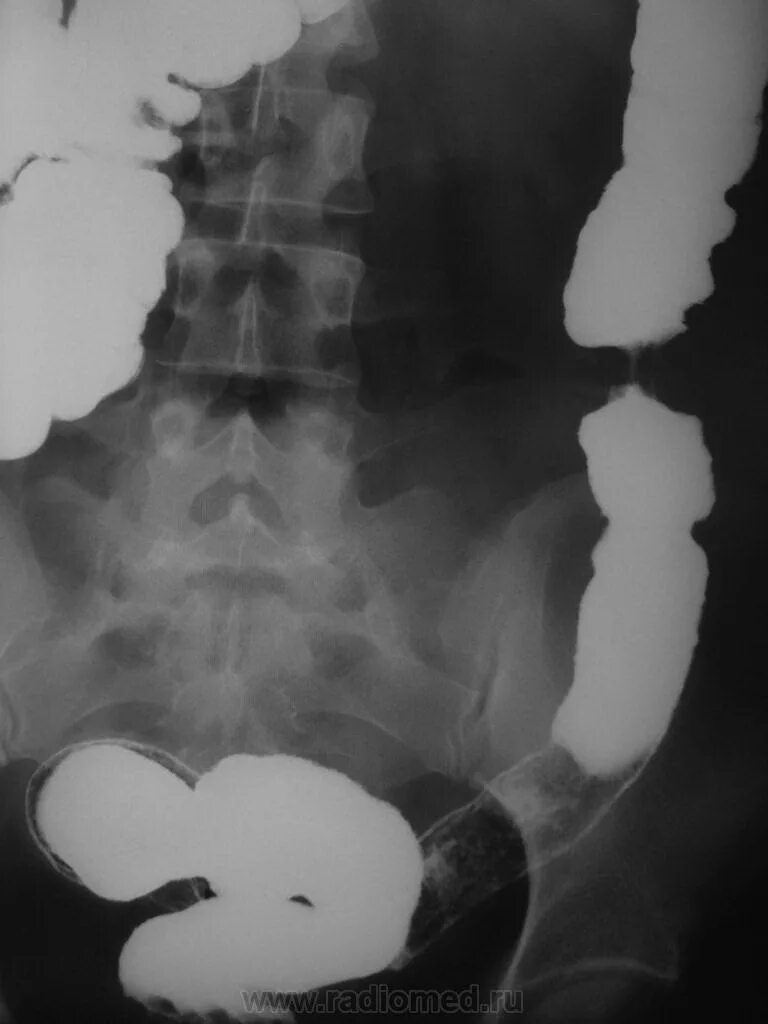

Ирригоскопия кишечника что показывает